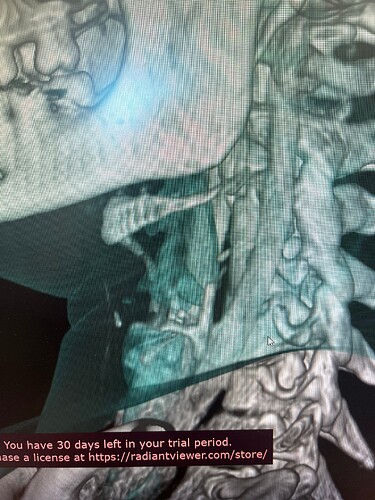

In your first & last pictures, you can see how close to your spine the greater horns of your hyoid are. Your whole hyoid looks like it’s been pushed back further in your neck than it should be possibly producing Hyoid Bone Syndrome (HBS).

Might want to check out left styloid process and ligament also. Can see it on the 3D but not all of it due to blood vessels. Might be contributing to the hyoid injury/problem if ligament is calcified.

So frustrating that you were doing well! The hyoid bone processes do look quite long & very close to your vertebrae, as the others have said, so worth looking in to if you can…